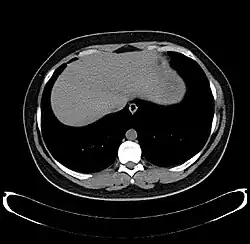

The diagnosis of liver disease is made by liver function tests, groups of blood tests, that can readily show the extent of liver damage. If infection is suspected, then other serological tests will be carried out. A physical examination of the liver can only reveal its size and any tenderness, and some form of imaging such as an ultrasound or CT scan may also be needed.

Sometimes a liver biopsy will be necessary, and a tissue sample is taken through a needle inserted into the skin just below the rib cage. This procedure may be helped by a sonographer providing ultrasound guidance to an interventional radiologist.[73]

-

Axial CT image showing anomalous hepatic veins coursing on the liver's subcapsular anterior surface[74] -